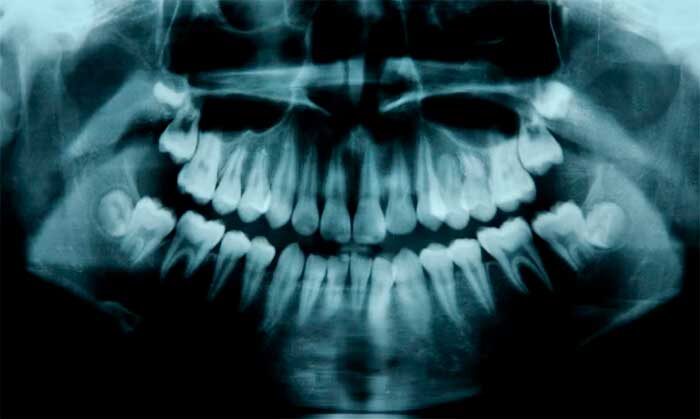

Рентген зубов у детей.